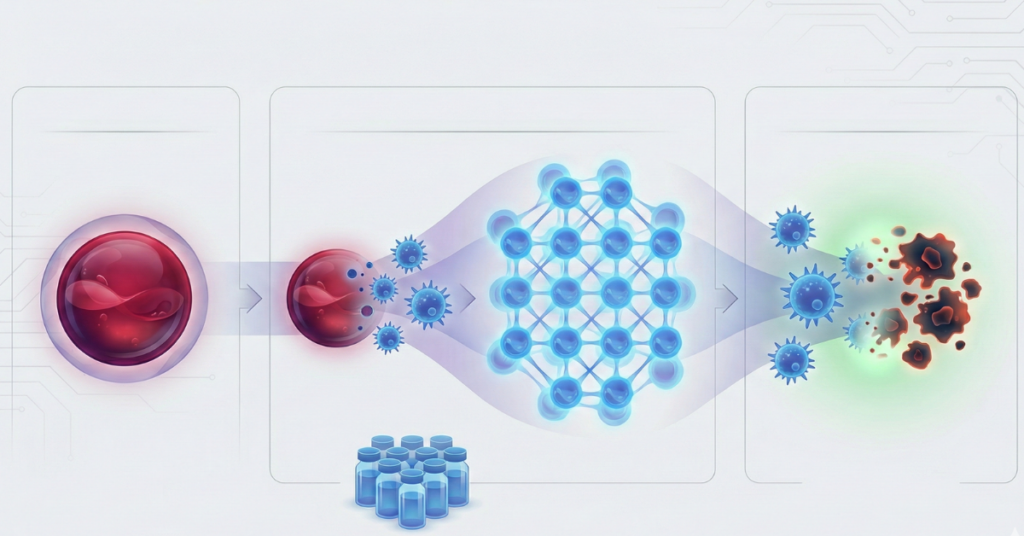

SUA sindrom, odnosno sindrom jedne pupčane arterije predstavlja određenu anomalliju koja nastaje u trudnoći. U pitanju je postojanje jedne pupčane arterije, umesto dve. Osim dve arterije, pupčana vrpca ima i jednu venu – kroz koju beba dobija sve što joj je potrebno od mame kako bi napredovala.

Sidrom jedne pupčane arterije znači da od bebe umesto kroz dve, samo kroz jednu arteriju otiče krv – što ne mora nužno predstavljati problem u razvoju fetusa. Ipak, preporučuju se češći pregledi i više potrebni analiza tokom trudnoće kako bi se pratilo stanje i bebe i mame.